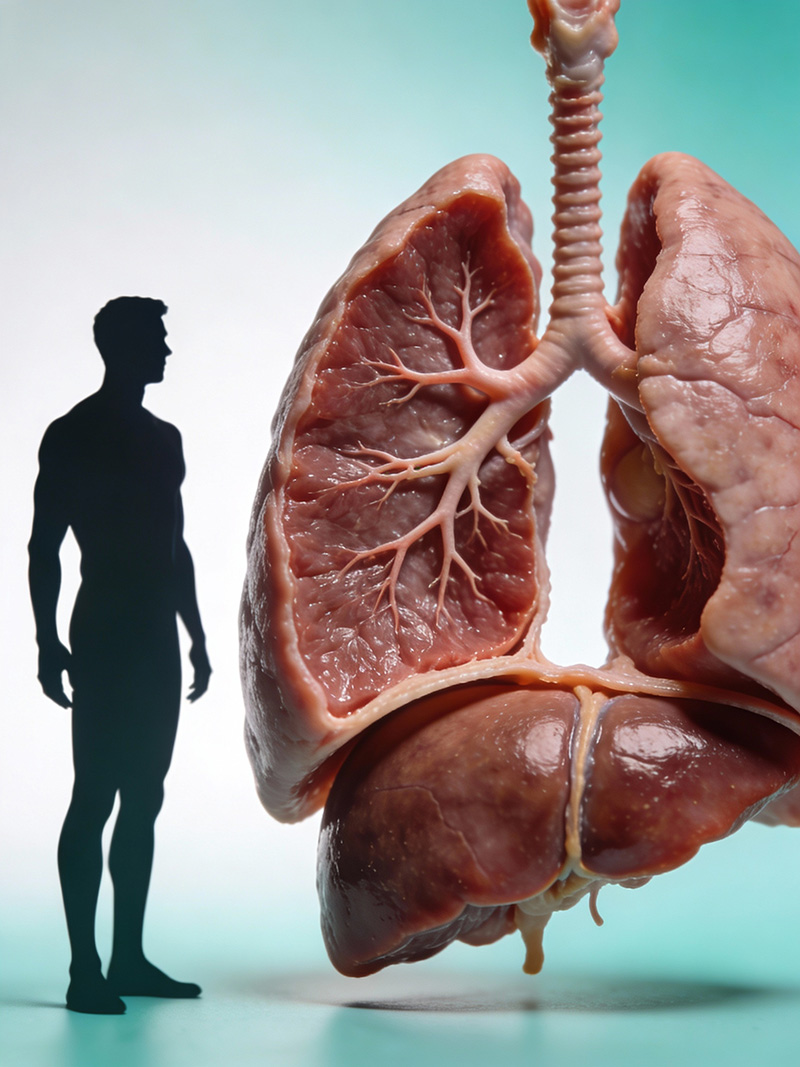

Wissenschafts- & Forschungskommunikation

Wir machen medizinische und wissenschaftliche Inhalte sichtbar – für Fachkreise, Entscheidungsträger und Öffentlichkeit.

Wir schaffen Visuals, die fachlich und visuell überzeugen – für Forschung, Ausbildung und Healthcare-Kommunikation

In unserer Galerie zeigen wir exemplarisch KI-basierte Bild- und Bewegtbildwelten aus verschiedenen Bereichen. Filtern Sie nach Themen – und sehen Sie, wie wir komplexe Inhalte in klare Visuals übersetzt haben.

Jedes Motiv ist ein Beispiel dafür, wie wirkungsstark KI-Bildproduktion und KI-Motion gezielt für Healthcare- und Wissenschaftskommunikation sein können.